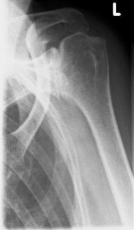

Abbildung11(2)Abbildung11

Fracture prostheses for complicated humeral head fractures

left: X-ray of a humeral head fracture before treatment with a fracture prosthesis.

right: X-ray of a humeral head fracture after treatment with a fracture prosthesis